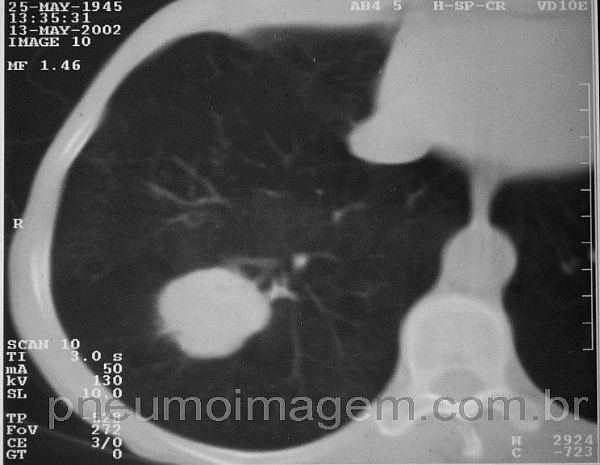

Veja imagens de câncer de pulmão no PneumoImagem,

clicando aqui.